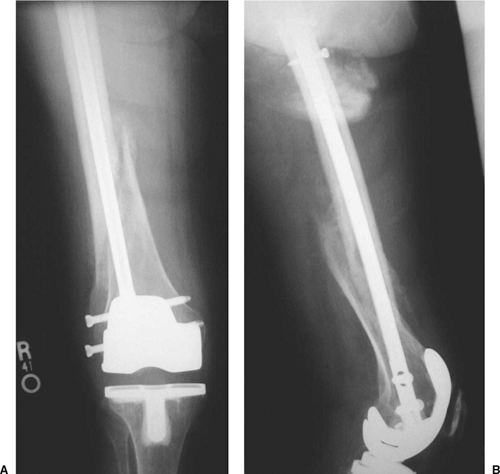

![]() |

Figure 45.4. AP (A) and lateral (B) radiographs of final revision construct with long-stem implant, struts, and multiple Luque wires.